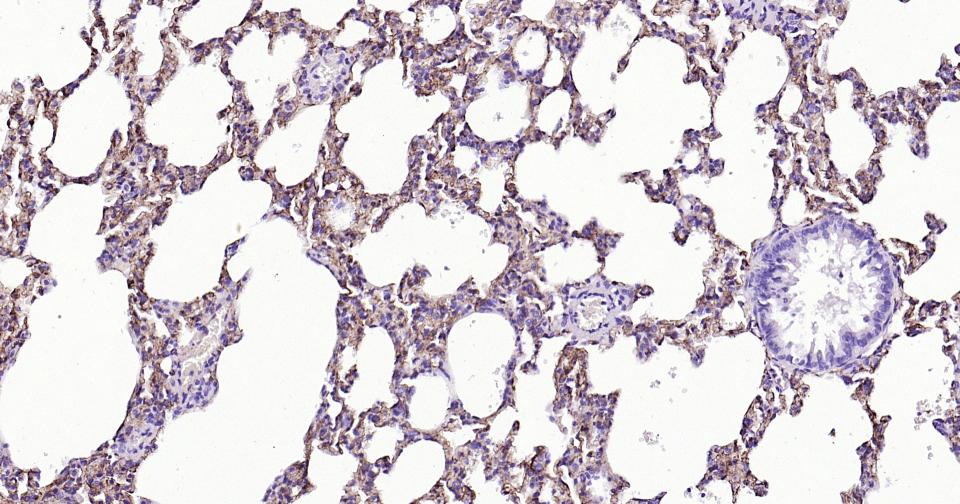

Paraformaldehyde-fixed, paraffin embedded Rat Lung; Antigen retrieval by boiling in sodium citrate buffer (pH6.0) for 15 min; Antibody incubation with Tau-4 Monoclonal Antibody, Unconjugated(bsm-41804M) at 1:800 overnight at 4°C, followed by conjugation to the SP Kit (Mouse, sp-0024) and DAB (C-0010) staining.

Paraformaldehyde-fixed, paraffin embedded Mouse Lung; Antigen retrieval by boiling in sodium citrate buffer (pH6.0) for 15 min; Antibody incubation with Tau-4 Monoclonal Antibody, Unconjugated(bsm-41804M) at 1:800 overnight at 4°C, followed by conjugation to the SP Kit (Mouse, sp-0024) and DAB (C-0010) staining.